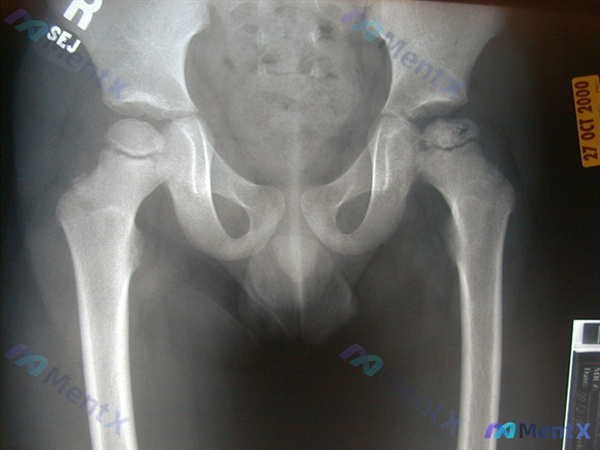

整理到一份4岁男孩的骨盆正位X光片资料,先不说最终分析方向,只看前期影像报告的描述: > 影像显示为幼儿骨盆正位片,双侧髂骨、坐骨、耻骨及髋关节区域显示完整,骨盆环对称; > 双侧髋臼顶圆滑,股骨头骨骺可见、形态对称,Shenton线连续; > 骨质分布均匀,未见明显骨折、脱位或破坏征象; > 盆腔...